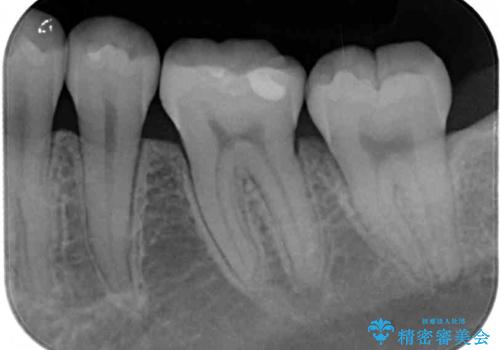

- 下の奥歯(右下7・左下7)にあって目立ってしまう銀歯を白くしたいとのことで来院された患者様です。

セラミックインレーにて修復治療を行うこととしました。